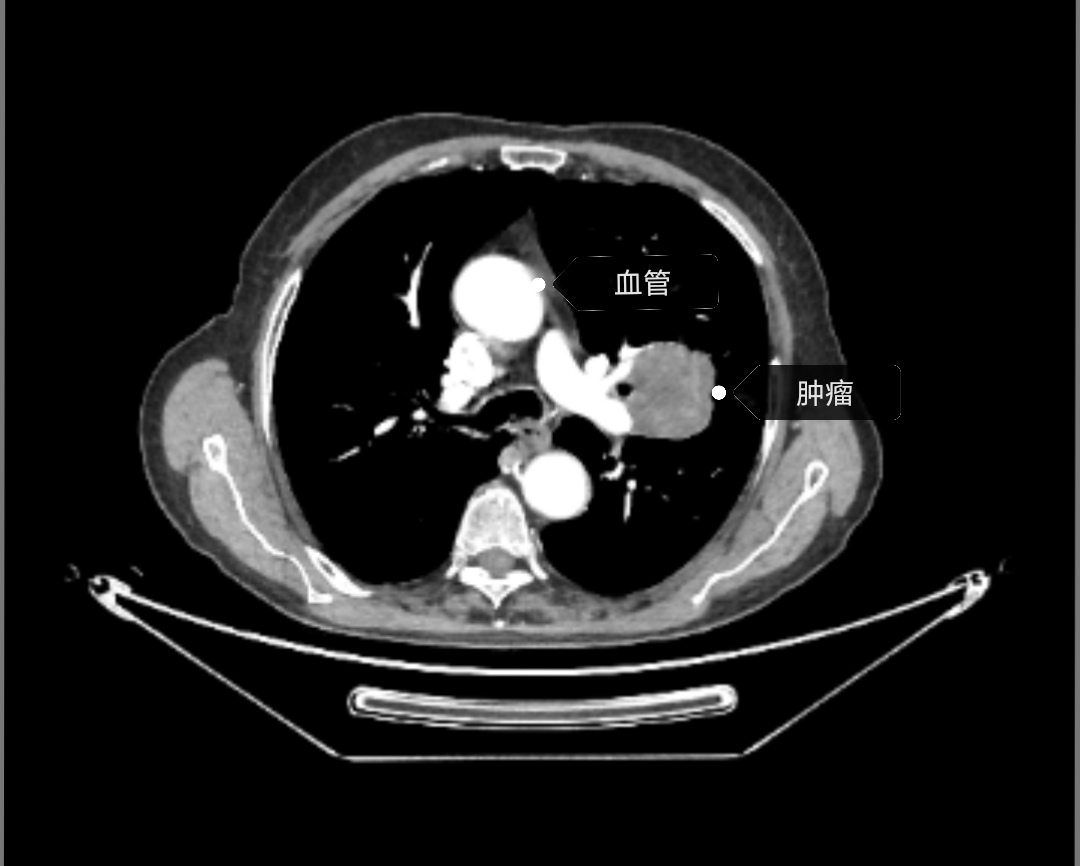

1.完善影像学检查:首先要完善CT检查,要做强化CT检查,而且要完善颅脑、胸部、腹部的强化CT检查。因为强化CT能看清肿瘤的血运情况,更能清晰的判断肿瘤的良恶性程度,还能看清肿瘤淋巴结的情况以及肿瘤同血管的关系。颅脑、腹部强化CT的检查主要是为了排除转移;如果有条件的病人头部可行磁共振检查。因为如果发现转移病灶以后病人的分期和治疗方案是不同的。

白色的是血管,灰色的肿瘤